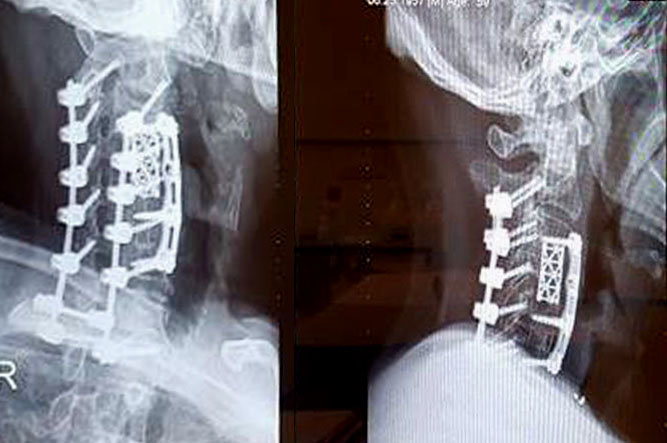

I was rolled into the operating room on the same week of Halloween. Just as I was going under, I played back in my mind, step by step, on how the surgeon was going to extract the calcified material that was lodged against the riskiest part of my cervical spine. The traditional practice for relieving compression is to go in through the back of the neck but there were dangerous complications in my case because the calcified material practically surrounded my spine. That was the reason why most other doctors would not have taken my case. Thank the good Lord, for this surgeon, because he was inspired to go through the front door, so to speak. He sliced open the front of my neck (this was where the radical part came in), then he literally removed the C4 bony segment of my cervical spine. Afterwhich, he and another doctor carefully scraped off the hardened material that was pinching the frontal section of the cord. From there, they shored up the missing bony segment with a titanium cage and a screwed-on plate. Check out the X-ray image below. [By the way, the bone will grow back encompassing the cage.]

Around Thanksgiving2, I underwent 2 more operations. The second one was not exactly in the original plan, but I’ll talk about it another time. In the third procedure (which was supposed to be the second one, haha), the surgeons cut open the back of my neck and proceeded to correct the rest of the compression. After which, the doctors added more implants. I actually woke up for a short period of time and felt the drilling of one of the titanium screws. Fortunately, the anesthesiologist was on the ball and I was back in dreamland. When I came out of recovery, they told me everything went well.